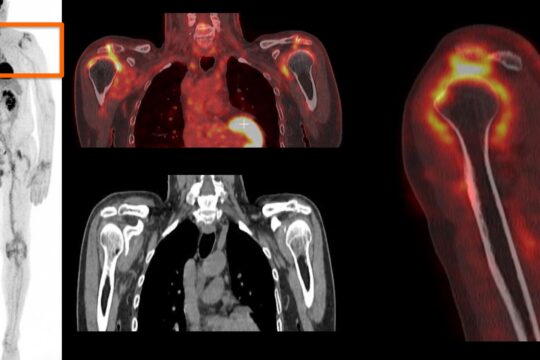

Les douleurs d’épaule représentent le 3e motif de consultation pour douleurs musculosquelettiques et

Des recommandations d’Aout 2023 sur la place de l’examen clinique et du bilan para clinique dans la démarche diagnostique pour une PEC de 1ere intention optimisée : Leur application en pratique

1/ revoir l’examen de l’epaule

2/ à partir d’un audit clinique et de mises en situation clinique,

• les signes discriminants orientant votre diagnostic à l’interrogatoire et à l’examen clinique

• Examens paracliniques à réaliser pour confirmer ou réorienter votre diagnostic,

• Repérer les éléments devant conduire à une consultation spécialisée et les signes de gravité devant la faire rechercher en urgence.

• A partir de cette démarche, définir les modalités de prise en charge de première intention.